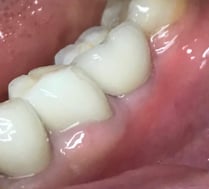

Coroa instalada em boca

COROAS E FACETAS DE PORCELANA UNITÁRIAS

As coroas ou lentes de porcelana também tem ampla indicação em casos unitários : dentes fraturados, escurecidos após tratamentos de canal, alterações de forma e manchas que não respondem ao clareamento, são exemplos de situações em que precisamos harmonizar esse novo dente com os vizinhos.

Espelhar um dente vizinho com uma nova coroa ou faceta de porcelana, é um procedimento altamente técnico, que requer a habilidade e experiência de um dentista estético e de um laboratório qualificado.